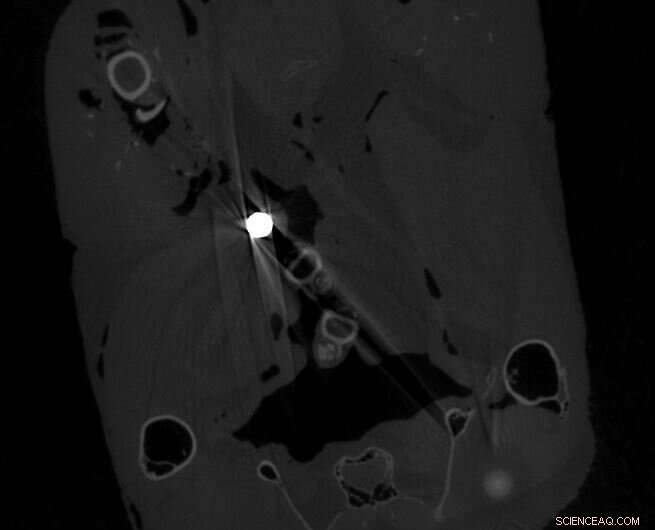

The large white dot is a whole shotgun pellet and smaller white dot is a lead fragment. Credit: University of Cambridge

This shows a whole shotgun pellet, a small metal fragment and a probable bone fragment. Note the obvious artifact effect around the shotgun pellet. Credit: University of Cambridge

The researchers used a high-resolution CT (computerized tomography) scanner to locate the lead fragments in the pheasant meat in three dimensions, and measure their size and weight. The meat was then dissolved, allowing the larger fragments to be extracted and analyzed further to confirm they were lead.

An average of 3.5 lead pellets and 39 lead fragments of less than 1mm wide were detected per pheasant. The smallest fragments were 0.07mm wide—at the limit of resolution for the CT scanner for specimens of this size—and the researchers say it is likely that even smaller fragments were also present.

The lead pieces were widely distributed within the birds' tissues and some of the small fragments were over 50mm from the nearest lead shot pellet.